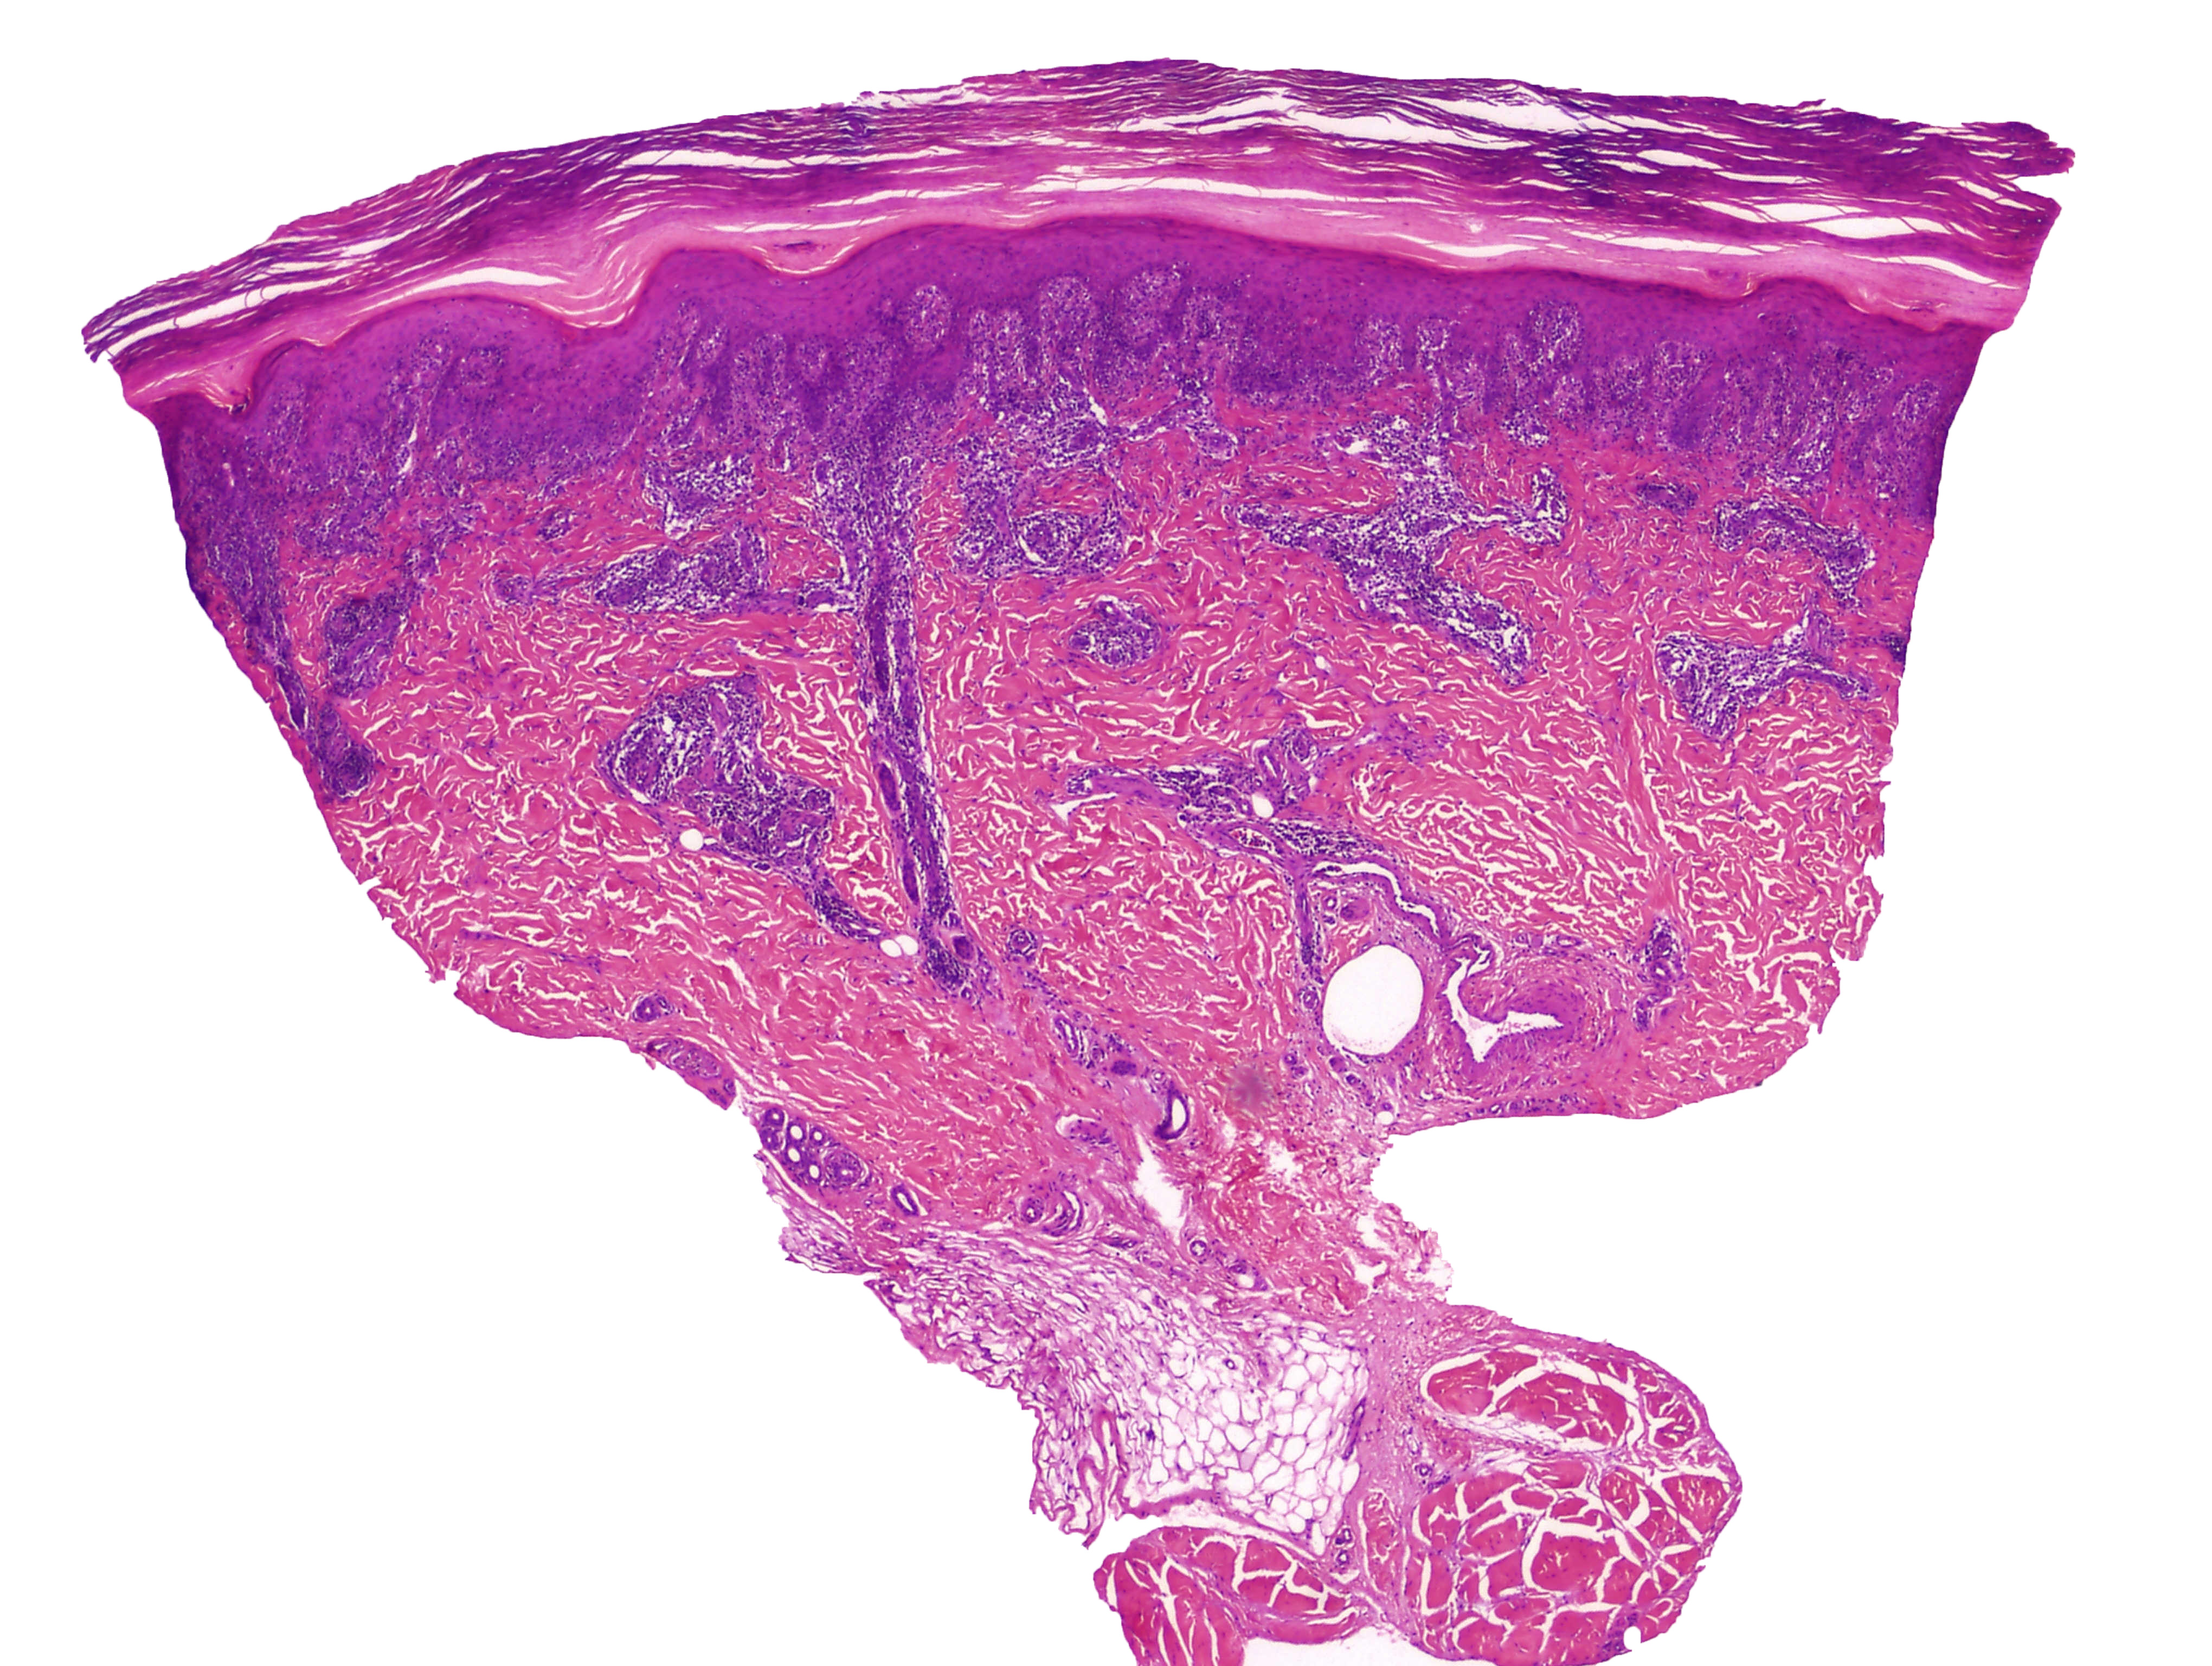

Cas dermatopatologia. Dona de 61 anys amb un àrea hiperqueratòsica vulvar

Març 2013

La biòpsia mostra una proliferació intraepitelial de cèl·lules de nuclis hipercromàtics i citoplasmes clars i abundants. A la porció més basal de dermis es disposen en grups, mentre que a dermis alta apareixen aïllades i són visibles fins i tot a la capa còrnia.